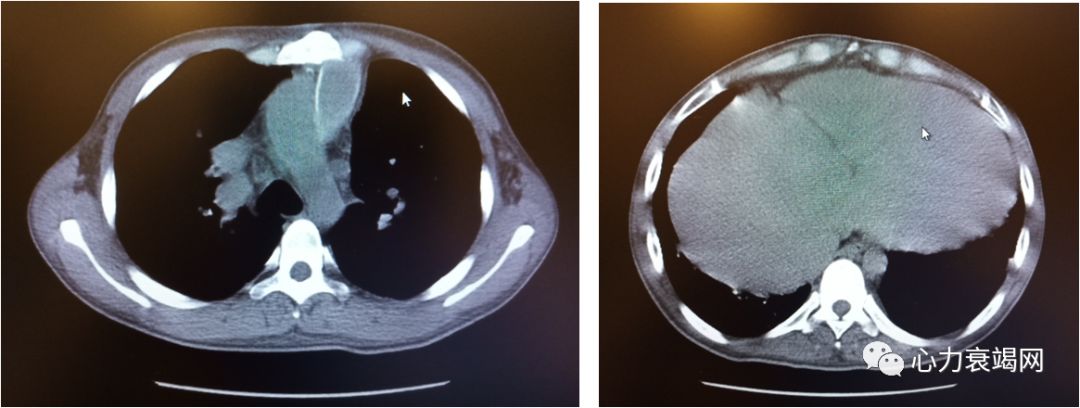

CT